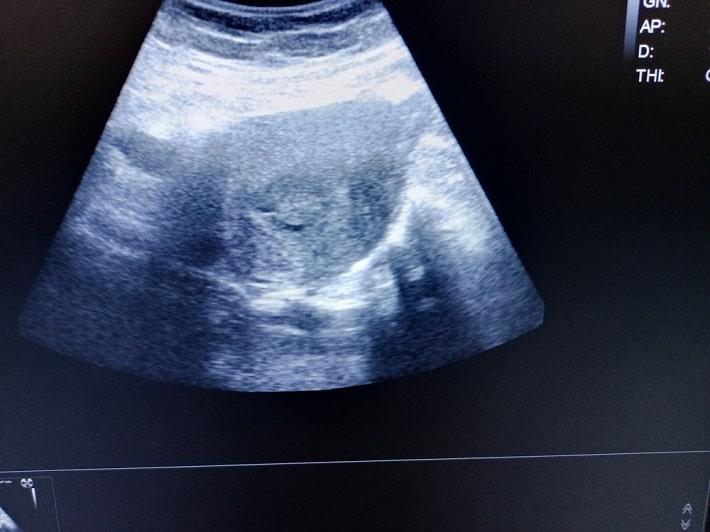

קשה לענות על שאלה זו. מאחר שפוליפים ברחם הם פעמים רבות אסימפטומטיים, כלומר אינם גורמים לתסמינים, ונשים רבות עם פוליפים ברחם יכולות לא להיות מאובחנות לעולם2.פוליפ ברחם בדרך כלל מתגלה בבדיקת אולטרסאונד אצל רופא או רופאת נשים, ובמרבית המקרים יתגלה יותר מפוליפ אחד. בדרך כלל פוליפים נשארים בתוך הרחם, אבל הם יכולים לחמוק דרך פתח הרחם ולגרום להופעה של פוליפ בצוואר הרחם או בתוך הנרתיק[1].

שאלה: זה כחודש אני סובלת מדימומים בלתי פוסקים. הרופא שלח אותי לבדיקת אולטרסאונד וגינלי למרות הדימומים והממצאים הם: בתוך חלל הרחם נצפה ממצא סולידי בגודל 148 מ"מ (פוליפ אנדומטריאלי במקום ראשון) קוטר בחתך רוחבי: 15 מ"מ. בשחלה שמאלית נצפה ממצא